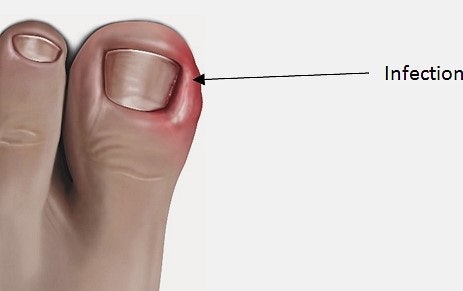

관통 발톱이 발생할 때, 큰 발가락이 빨간색으로 변하며 부풀어진다.이 주에서는 지속적인 마찰, 조직 성장, 조직 성장을 유발한다.극단적인 고통 때문에 보통 걷는 것이 어려운 경우에 따라 걷잡을 수 없다.자세한 내용은 그들을 절단하는 습관이다.발가락에 과도한 압력을 적용하지 않지만, 단순히 잘라내는 습관이 될 수 있지만, 단순히 잘라내는 습관이 될 수 있다.타원형의 모양을 잘라내면, 발톱은 수직적으로 자랄 수 있는 것보다 옆으로 자랄 수 있습니다.이것은 염증을 유발한다.이것은 마치 이런 것 같은 손톱이 좋아하는 손톱입니다.소개의 또 다른 원인은 태국의 발명의 선수가 되었다.선수가 오랫동안 방치되어 있기 때문에 정보가 남아 있기 때문이다.운동선수들의 발바닥에 감염으로 인한 곰팡이가 발생되는 곰팡이 질환이다.이 선수는 피부만 침투하지 않지만 세부사항은 피부뿐만 아니라 세부 사항입니다.

운동이나 약을 복용하거나 적용 등 마약을 취급하지 않더라도 쉽게 치유하지 않는 이유는 건강에 해로운 박테리아와 관련이 있다는 점이다.여름 계절 접근 방식은 비가 올 시즌까지 상승하고 습도가 높아지면, 태아의 염증이 확산되면서, 결국 악화될 가능성이 높다.큰 문제는 더 큰 문제가 되는 것은 드문 일이다.신경세포는 존재하지 않는 발톱에 나타나기 때문에 뒤늦게 인식된다.따라서, 많은 사람들은 그들의 발명에 따른 세부 정보를 도입하고 싶어 하는 경우가 많다.